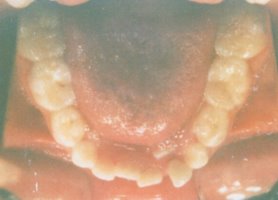

This is the five year follow-up for the

patient in the pictures above. No further orthodontic treatment was

performed after the retainers were removed. Since adequate space was

created during a growth phase, her lip and tongue muscles were able to

adapt to the larger size. The teeth were able to settle into their most

natural position without the use of braces since they were not impeded

by crowding. |